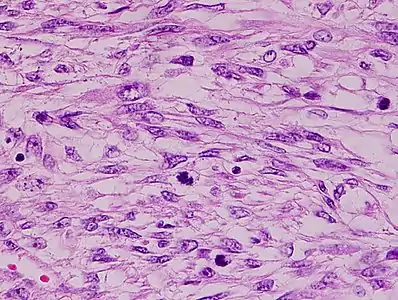

The tumors are usually hemorrhagic and soft and microscopically marked by pleomorphism, abundant (15–30 per 10 high-power fields) abnormal mitotic figures, and coagulative tumor cell necrosis. The differential diagnosis, which includes spindle cell carcinoma, spindle cell melanoma, fibrosarcoma, malignant peripheral nerve sheath tumor and even biphenotypic sinonasal sarcoma, is wide.

- Histopathology of leiomyosarcoma shows variable atypia, often with cytoplasmic vacuoles at both ends of nuclei, and frequent mitoses.[11]